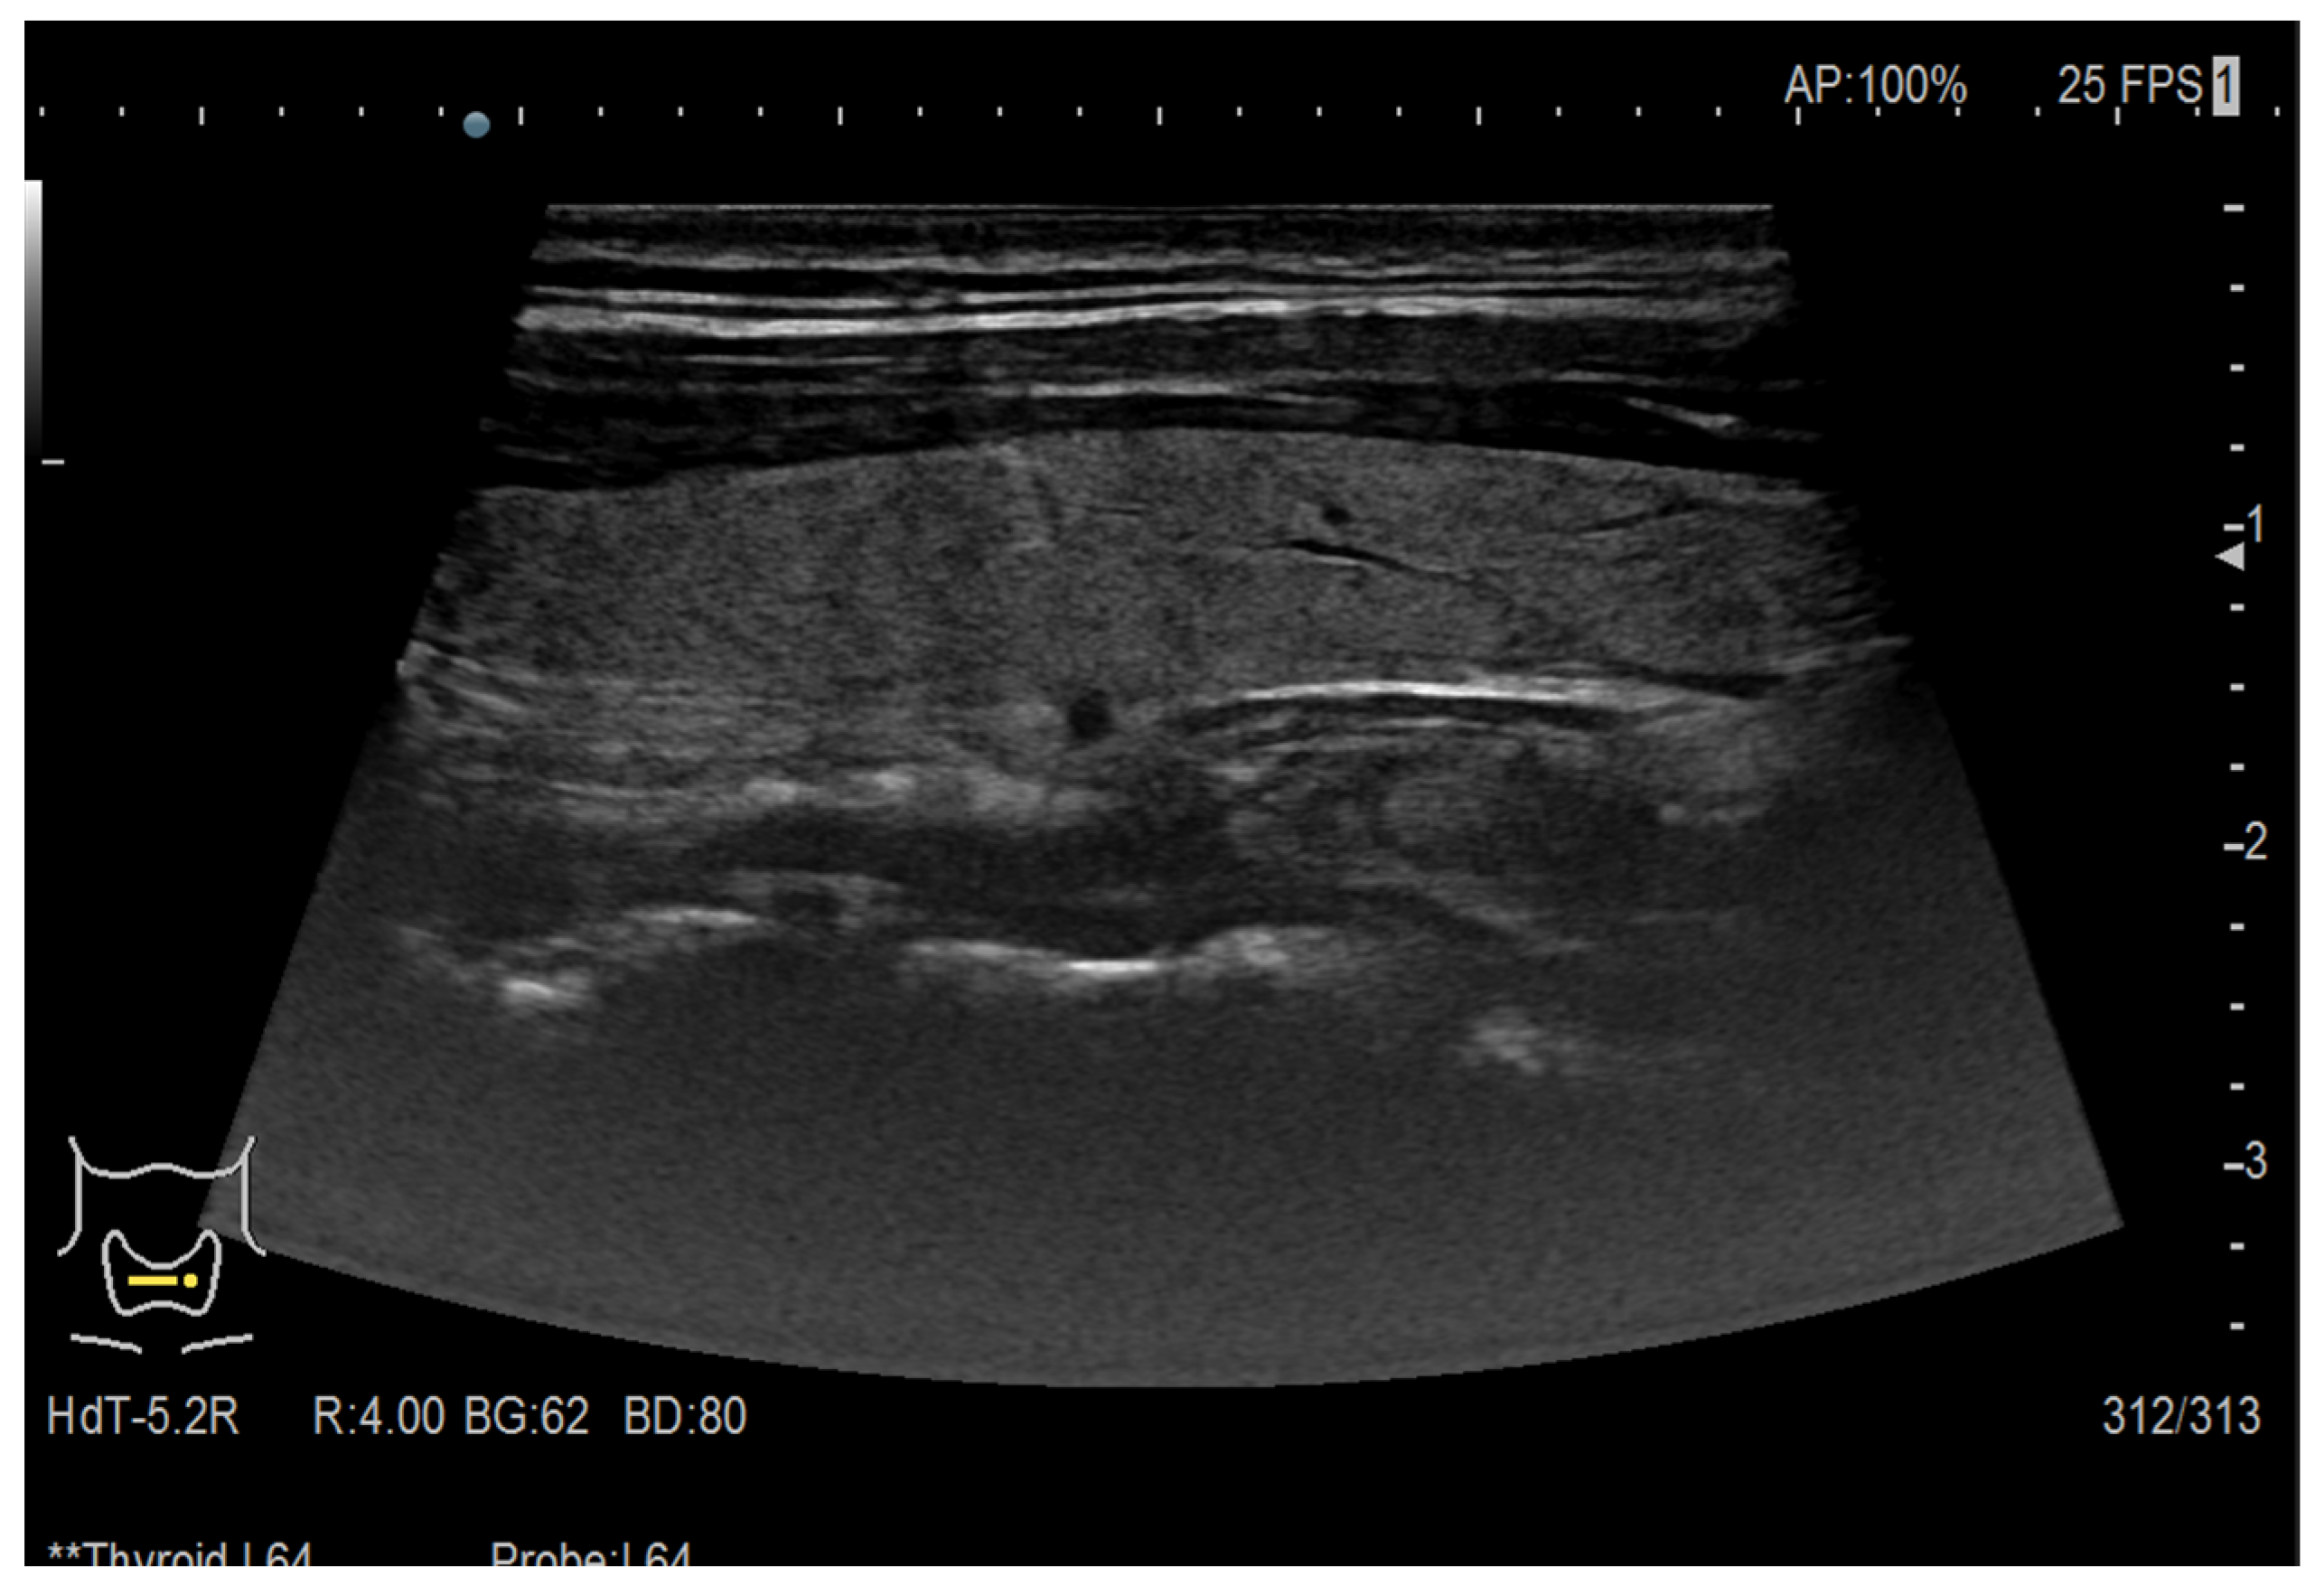

2.1. Ultrasound Images

2.1.1. The Data

3.1. Thyroid Nodule Diagnosis Based on Ultrasound Images: Binary Classification Problem Solved Using Convolutional Neural Networks